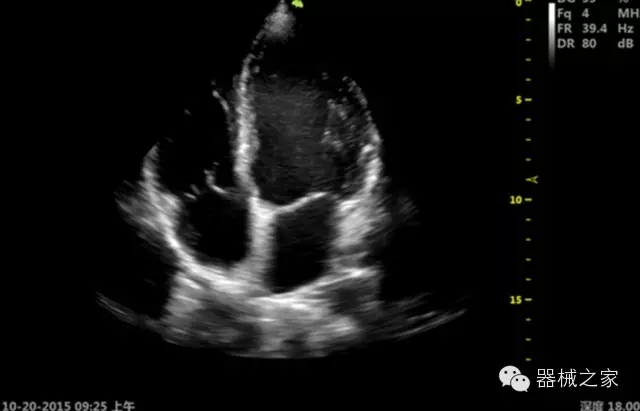

臨床圖片賞析